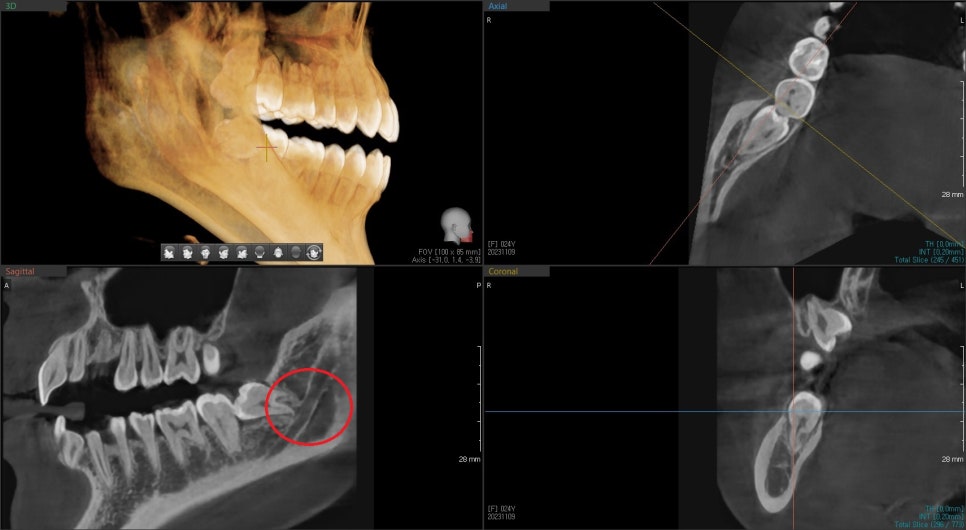

매복치 위치 평가를 위해 3D CT를 찍고 분석을 해봅니다.

아래쪽의 매복 사랑니는 신경관과 근접해 있고, 뿌리가 살짝 휘어있지만

발치에는 큰 문제는 없어 보입니다.

하지만, 발치 과정에서 잇몸 절개와 주변 골삭제는 최소 필요해 보입니다.